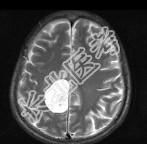

- 单项选择题男,68岁, 头痛头昏、左侧肢体肌力减退3个月余,请根据所提供图像, 选择最可能的诊断是 ( )

A、(右顶叶镰旁)血管外皮瘤

B、(右顶叶镰旁)转移瘤

C、(右顶叶镰旁)脑膜瘤(血管瘤型)

D、(右顶叶镰旁)胶质瘤

E、(右顶叶镰旁)恶性脑膜瘤